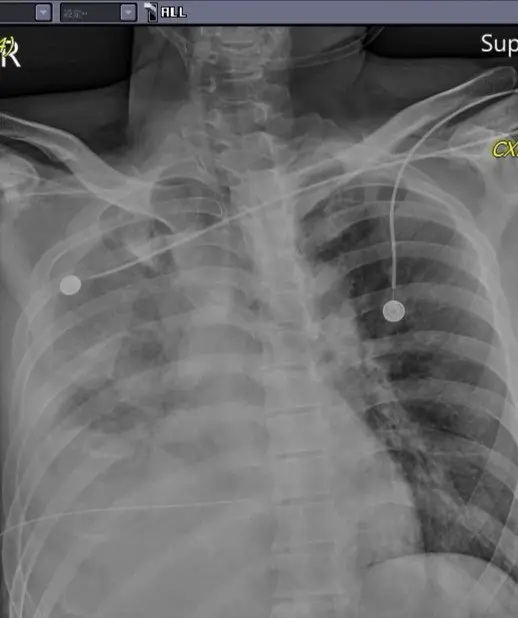

而在手術過程中,馮啟彥表示,不僅發現肺臟破裂引發氣血胸,而且因為利刃穿刺很深,橫膈膜及肝臟都有破裂及大量出血現象。所幸經過手術之後,病情已經比較穩定,3日上午林男雖然仍插著呼吸器,但已經能夠清醒的與大家致意。